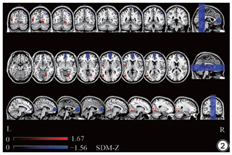

共纳入11篇研究(401例mTBI,371例健康对照)。基于元分析证实mTBI患者右侧舌回、左侧枕中回、右侧背外侧额上回和左侧中央沟盖的局部自发脑活动明显升高;左侧前扣带和旁扣带回、右侧角回和左侧额中回的局部自发脑活动降低(P<0.005,峰高Z>1,簇范围≥20个体素)。

基于主要的体素元分析显示mTBI患者较健康对照组的局部自发脑活动存在显著的异常改变。如表2和图2所示,mTBI患者右侧舌回、左侧枕中回、右背外侧额上回和左侧中央沟盖的局部自发脑活动明显升高。左前扣带和旁扣带脑回、右侧角回、右侧额中回的局部自发脑活动降低,如表2及图2所示。

敏感性分析表明,大多数脑区域都具有很高的可重复性。右背外侧额上回、左侧前扣带和旁扣带回、右侧角回、右侧额中回在10组数据中均可以交叉验证。右侧舌回、左侧枕中回、左侧中央沟盖在9组数据中可以交叉验证。异质性检验显示,右侧舌回、左侧枕中回存在显著的研究间变异,如表2所示。在发表偏倚分析中,Egger检验显示右背外侧额上回存在发表偏倚(P<0.05),其他大脑区域未发现发表偏倚,如表2所示。亚组分析显示大部分结果与主结果保持一致,如表3、4所示。